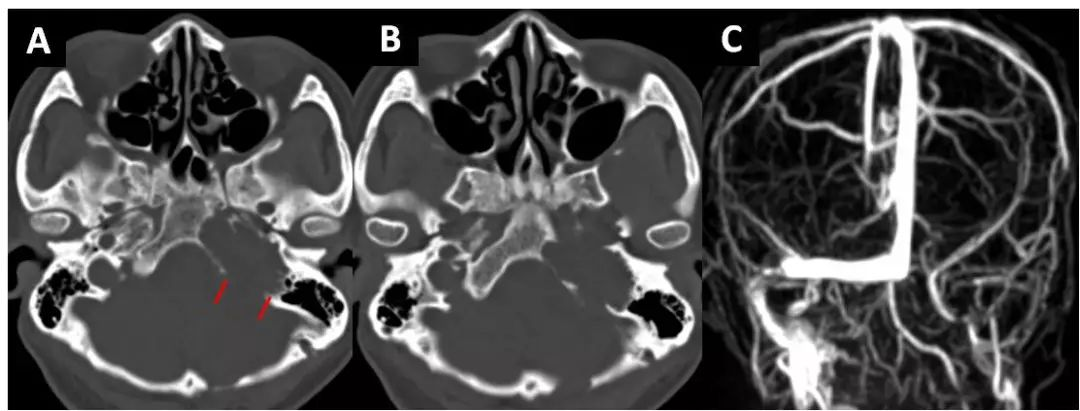

此患者是颈静脉孔内外沟通的神经鞘瘤,颅内肿瘤结节状,岩骨内肿瘤较多,且有一部分肿瘤生长至颈部。2年前已行乙状窦后入路,但未能全切。本次手术我们未选择乙状窦后入路,原因是岩骨内肿瘤较多,且颈静脉孔入口相对狭小(图8A,B),不利于岩骨内肿瘤的切除,二是颅内部分肿瘤位置靠内,体积不是很大,小脑半球遮挡较多,切除颅内部分肿瘤后,CPA不会向本组病例3那样提供一个很大的操作空间,颈静脉孔内的肿瘤很难切除干净,该患者颈部也有肿瘤(图11B),通过颅内-岩骨这个路径很难将颈部肿瘤切除。我们选择了耳科的岩枕经乙状窦入路,术前评估了静脉系统的代偿情况(图8C)提示右侧横窦及颈内静脉代偿良好。

图8. A,B术前岩骨CT可见左侧颈静脉孔扩大,岩骨破坏明显,但是颈静脉孔的入口较狭窄(红色标记);C术前MRV见左侧横窦及颈内静脉闭塞,右侧代偿良好。